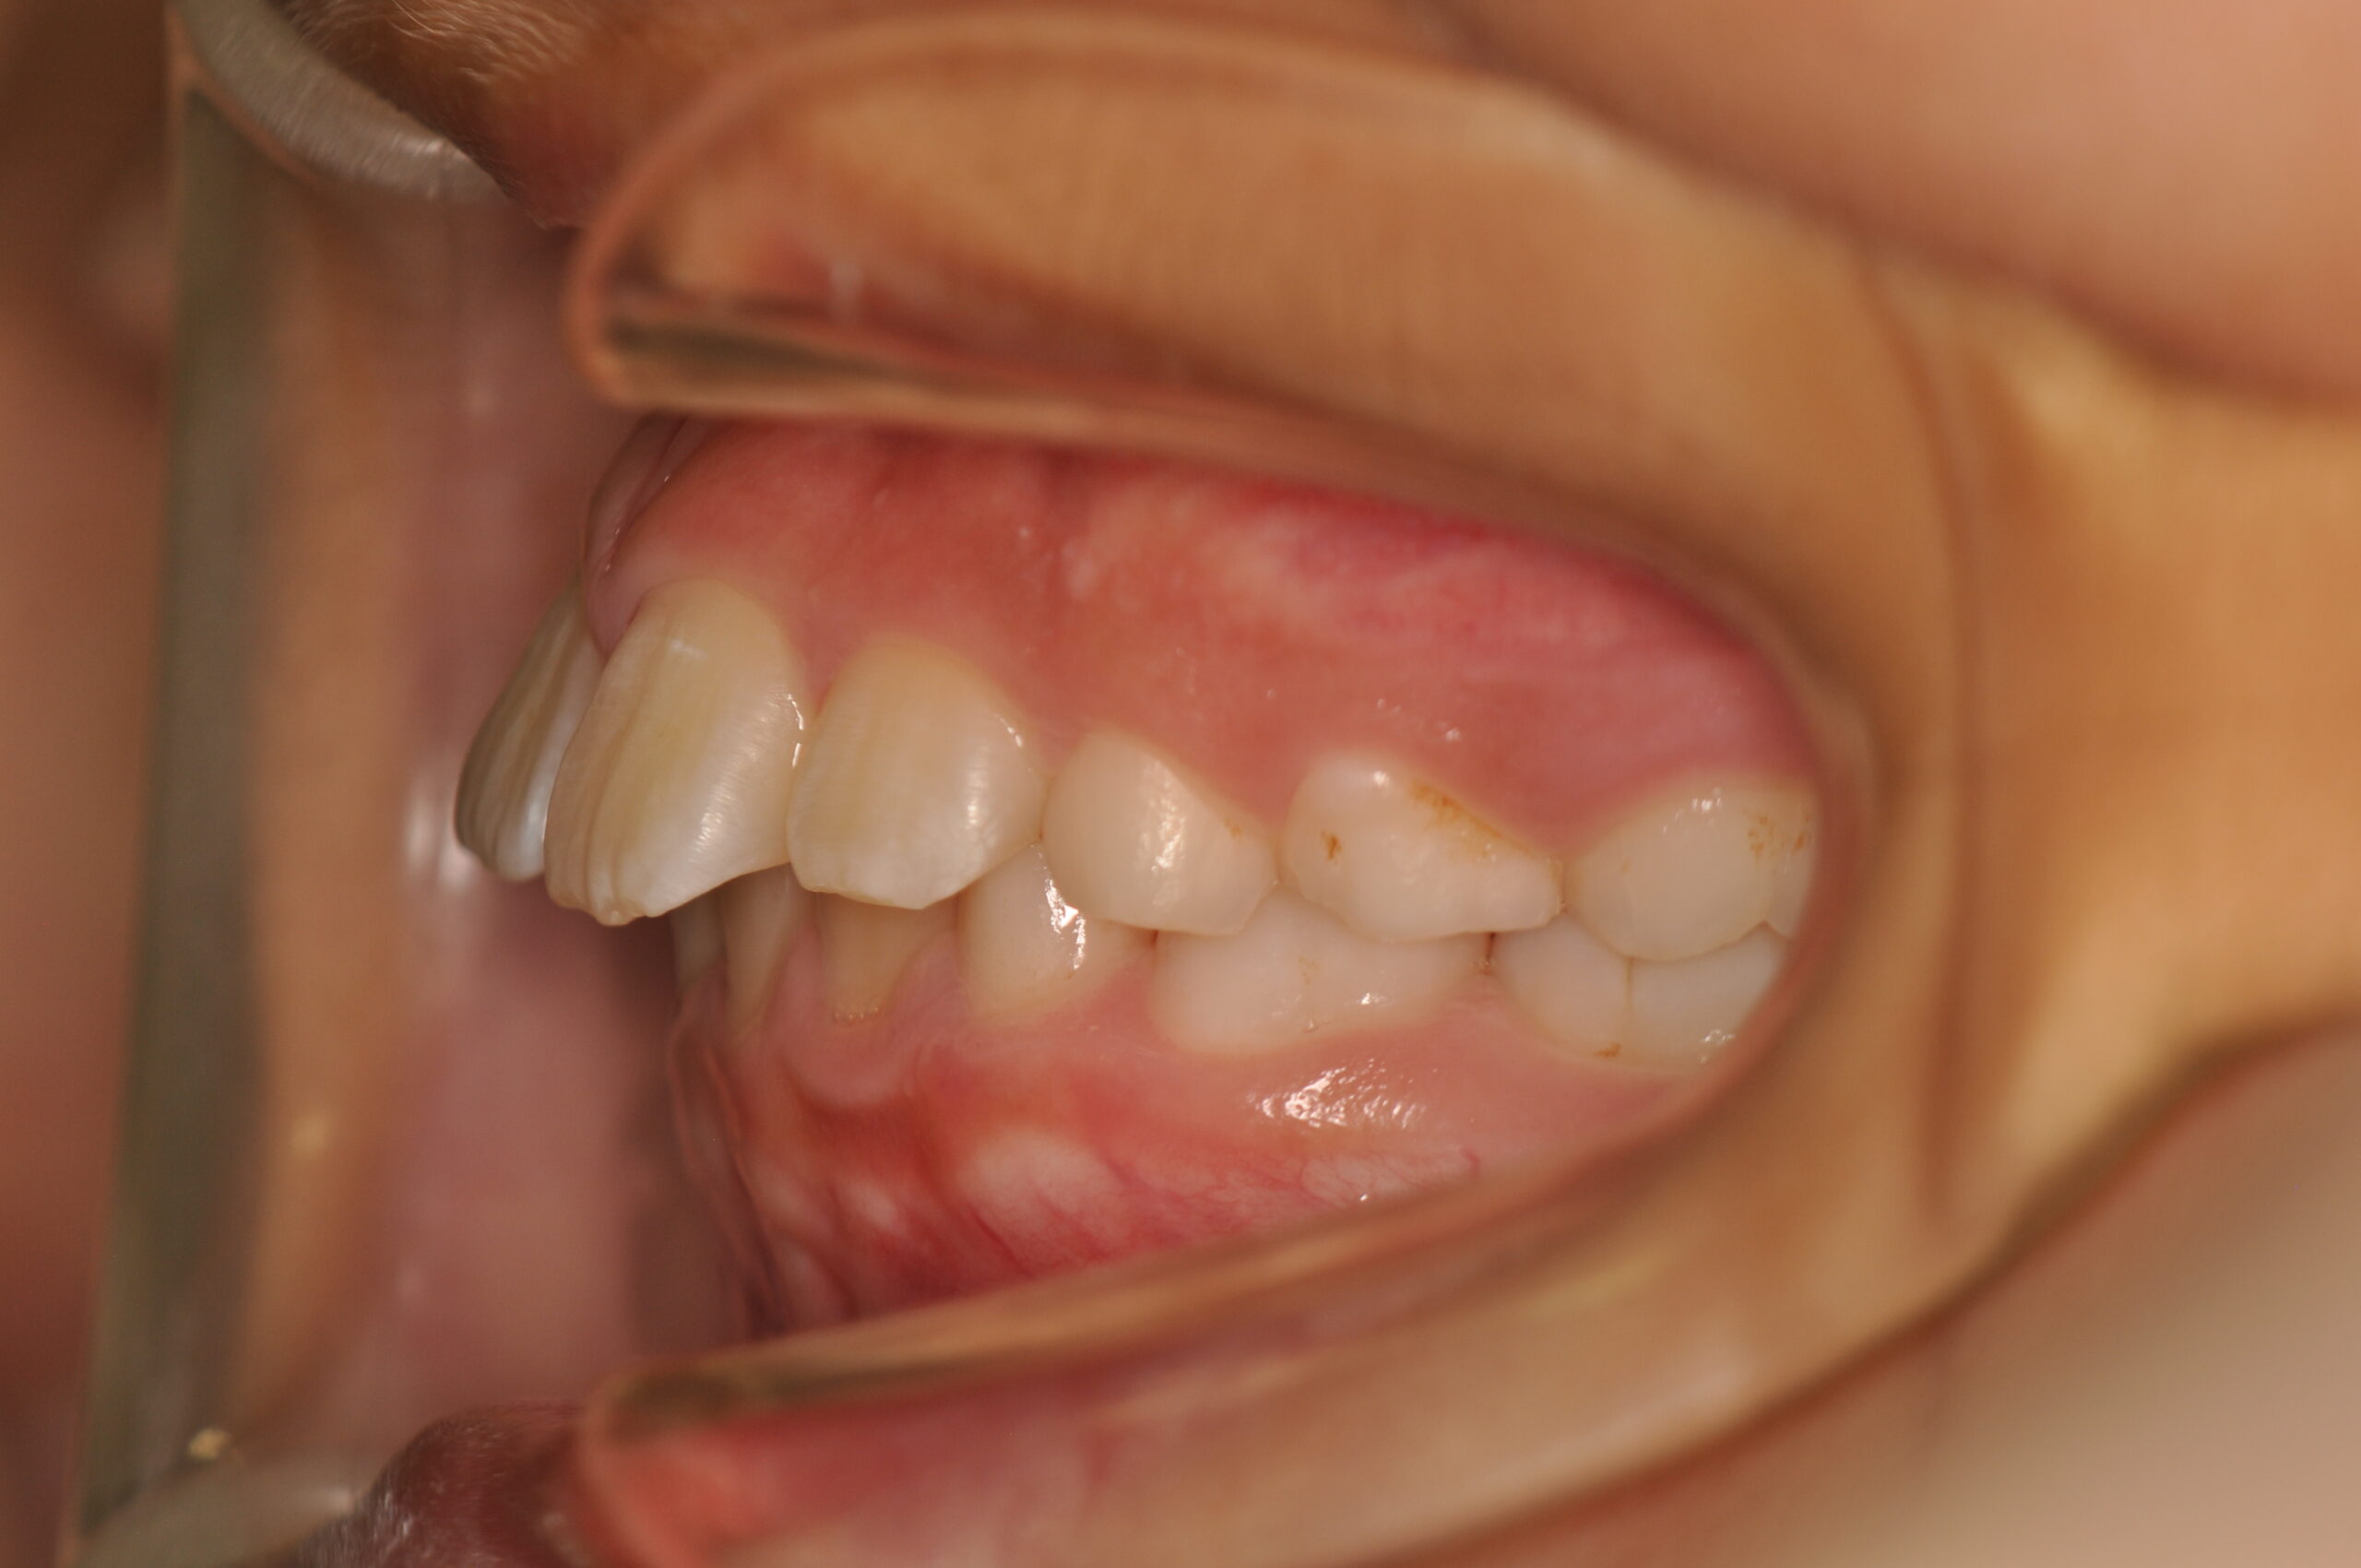

初診時

症例 症例 症例 症例

治療内容の詳細 初診時8歳の男性で、癒合歯があり今後の歯並びが心配で来院されました。

検査の結果、過蓋咬合、上顎前突を伴うアングルⅡ級1類不正咬合と診断しました。